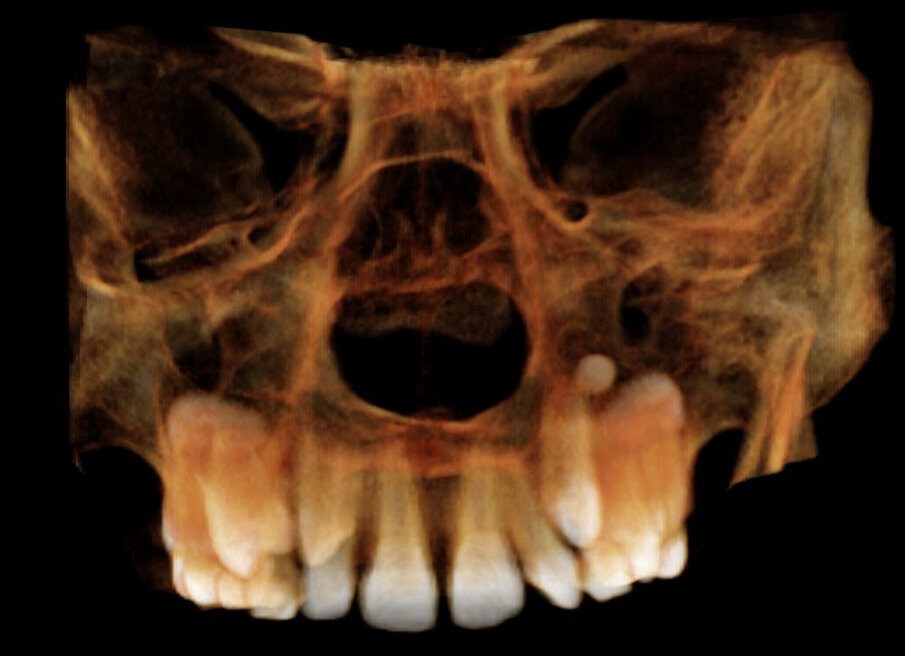

Alessandro, 8 anni, viene sottoposto ad una CBCT (Figg. 21, 22) dopo una valutazione iniziale dove si è riscontrato un percorso di permuta difficile dei canini permanenti (1.3-2.3).

Fig. 21_CBCT mascellare superiore.

Fig. 22_Dettaglio del percorso di eruzione dei canini.